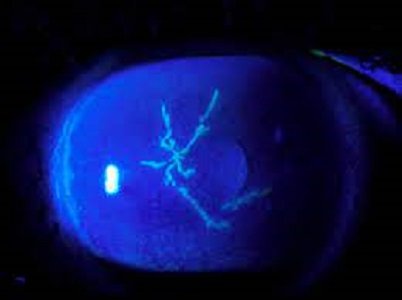

ان تینوں بچوں کی آنکھوں میں زخم بنا ہوا ہے جو سبز رنگ کا نظر آ رہا ہے اور اس زخم کے باعث آنکھ سے پانی آ رہا ہے